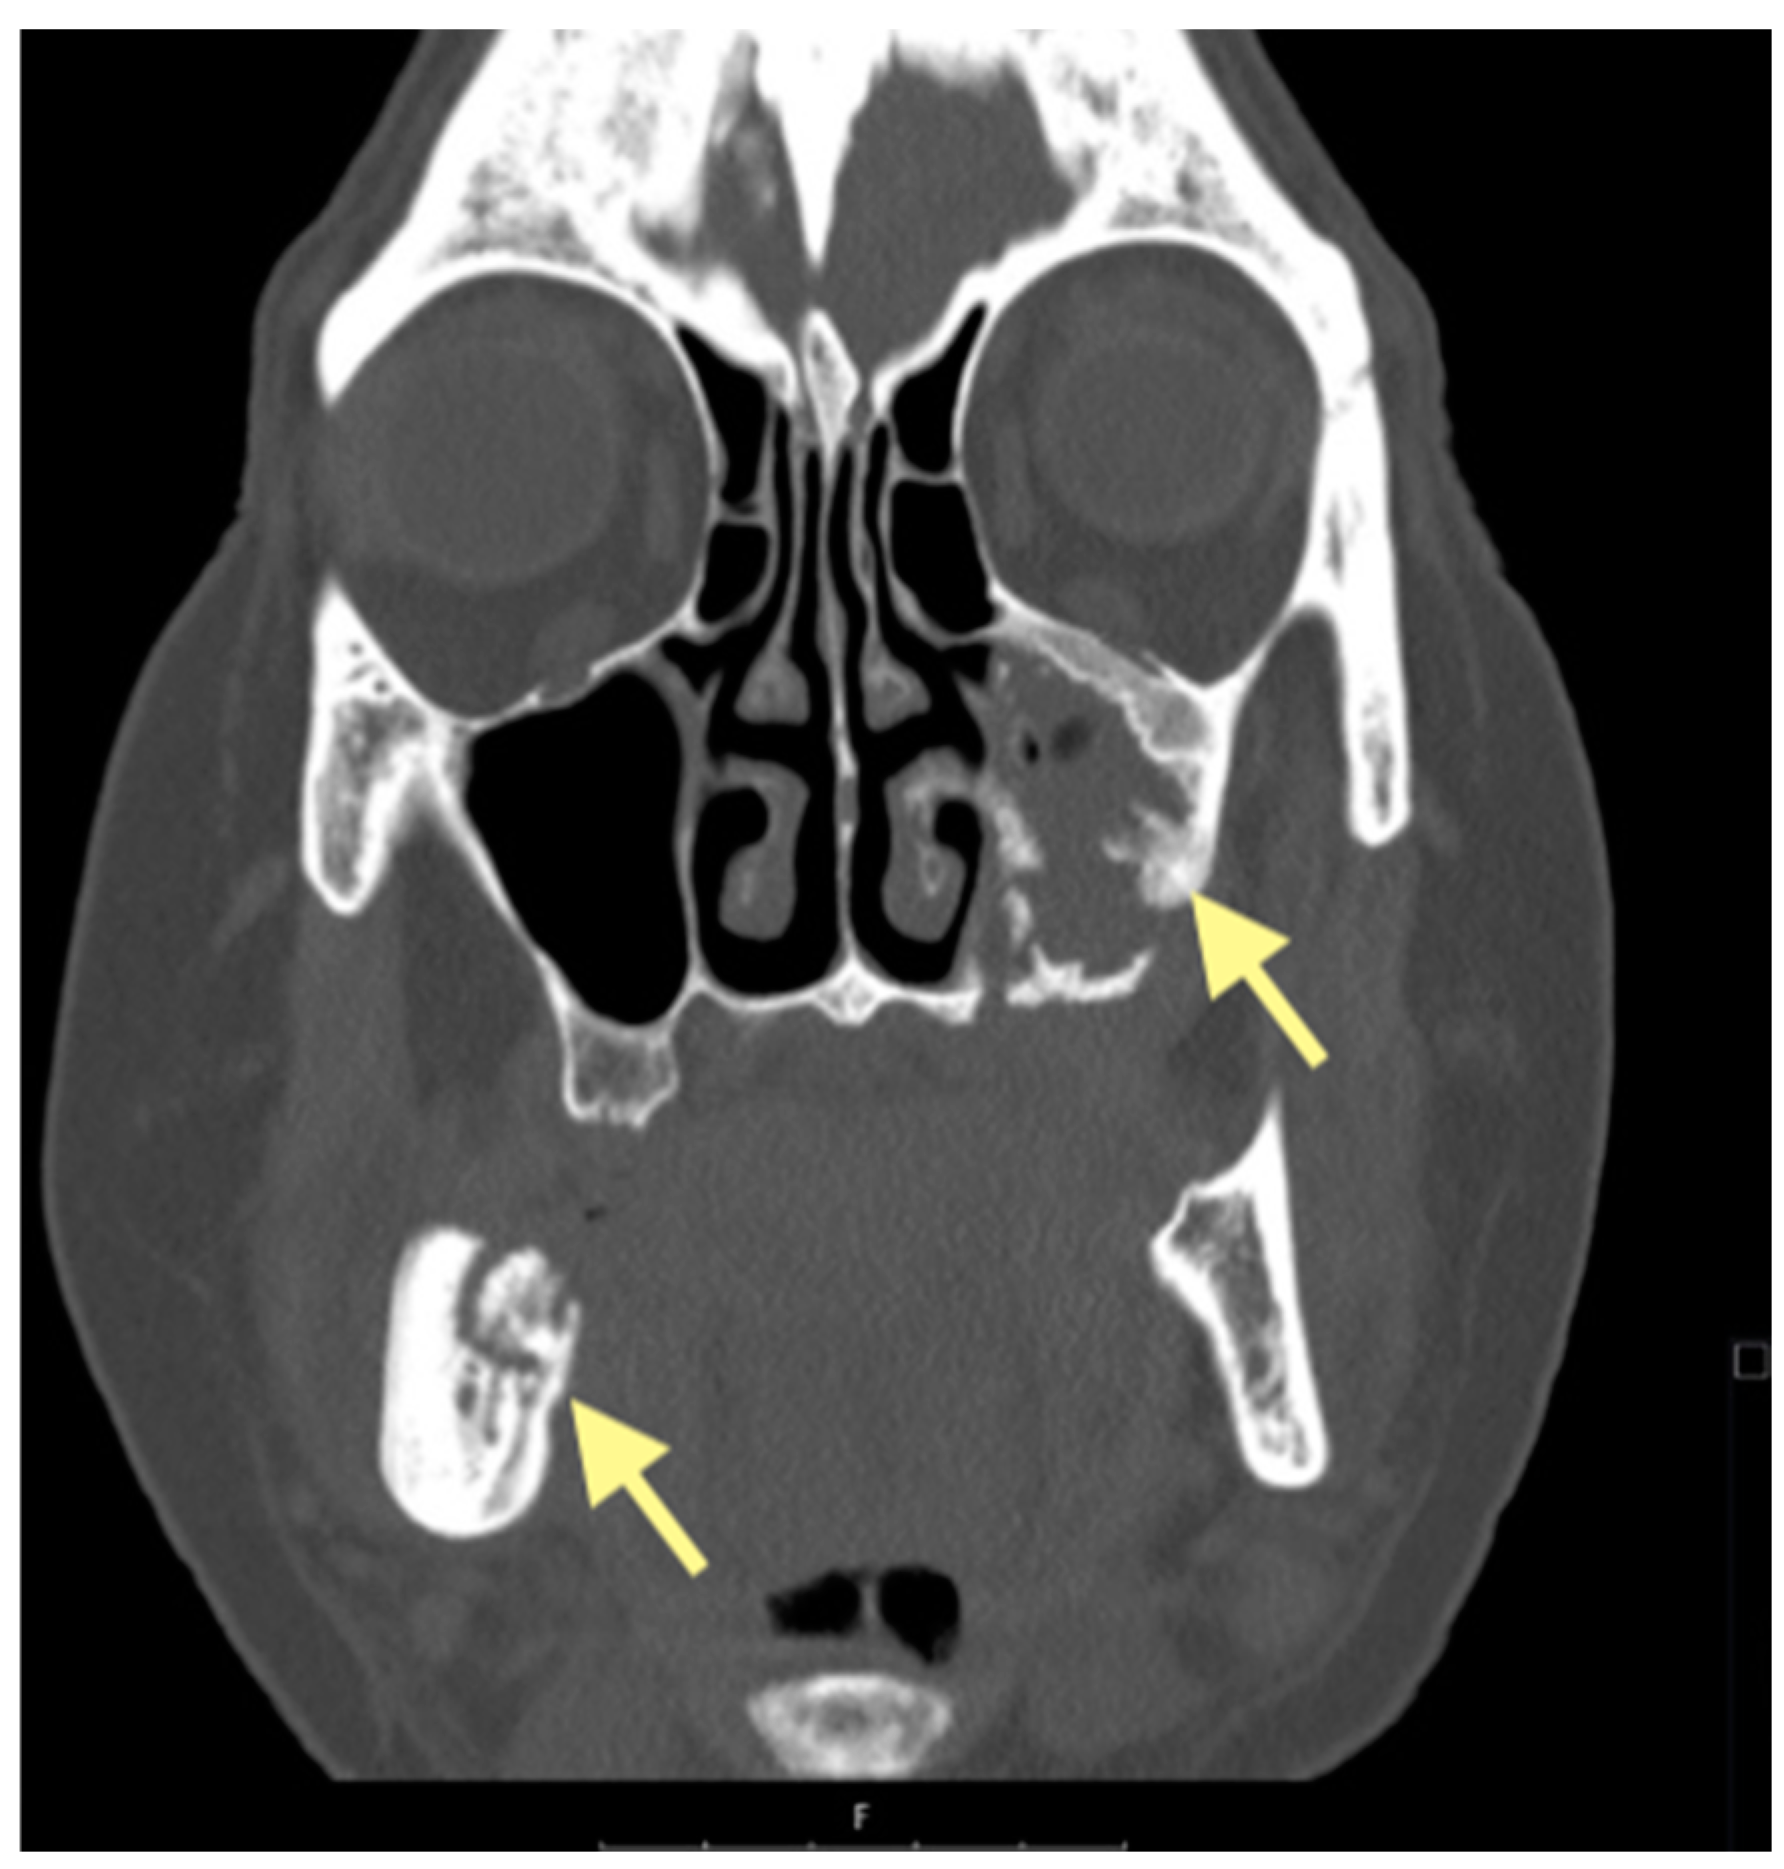

Figure 7.

CT of the head and facial bones (16 December 2024).

The third patient was a 75-year-old female with osteonecrosis of the mandible and maxilla in the fourth and in the second quadrant (see Figure 7, Figure 8 and Figure 9). The patient had third-stage jaw osteonecrosis. In 2023, the patient was diagnosed with osteonecrosis of the upper and lower jaw caused by antiresorptive therapy (until August 2021, the patient regularly used Zolendronic acid; then, this drug was replaced by the RANKL inhibitor Denosumab). The treatment was periodically complicated by submandibular and submental abscesses. In addition, due to the progression of the underlying disease, constant courses in chemotherapy were administered. The patient underwent three operations, which included sequestrectomy of the jaw with simultaneous use of A-PRF, antrotomy with revision of the maxillary sinus, closure of the oroantral communication, and opening and revision of abscesses of the soft tissues (see Figure 10 and Figure 11)